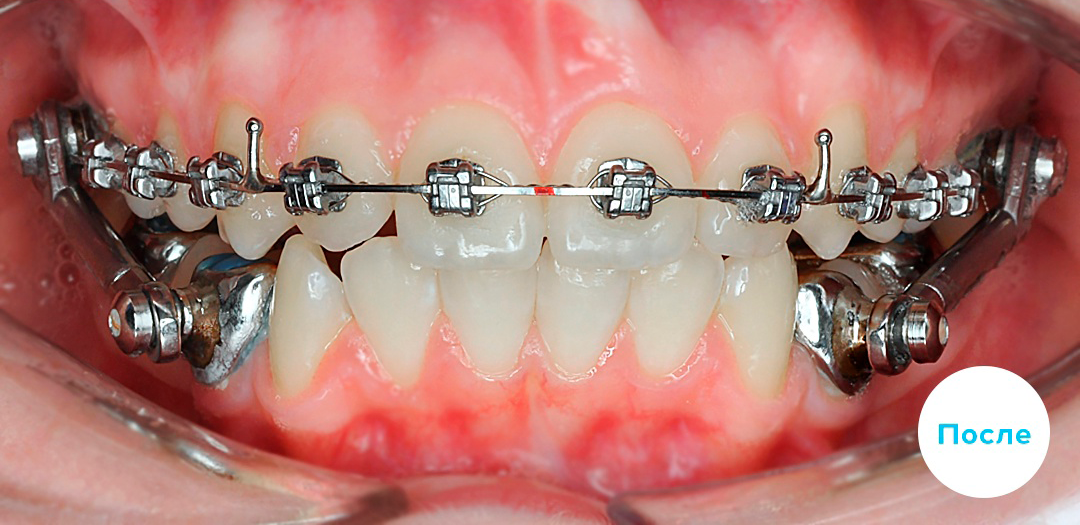

После

После

После